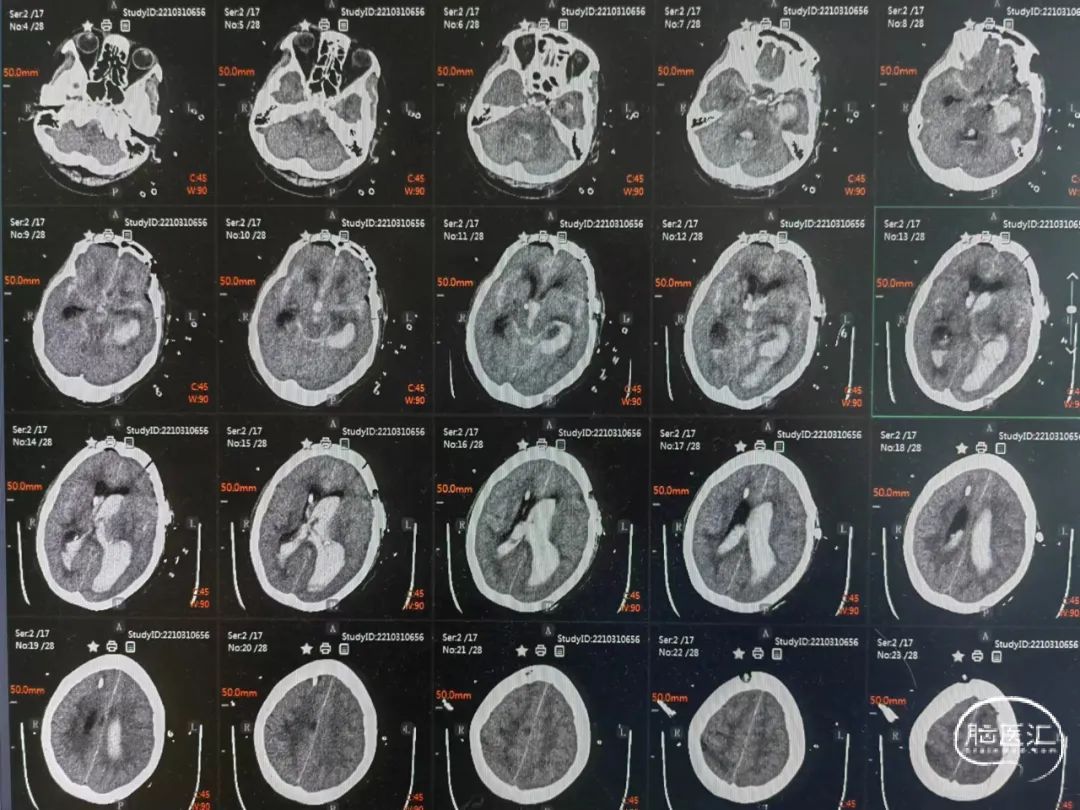

术前CT提示:脑内血肿,蛛网膜下腔出血。

术后第1天头颅CT提示:脑室系统积血较多,安排床旁锥颅脑室钻孔引流,尿激酶液化血肿。

术后一周头颅CT提示:脑室系统积血较前明显减少,更换腰大池置管引流。